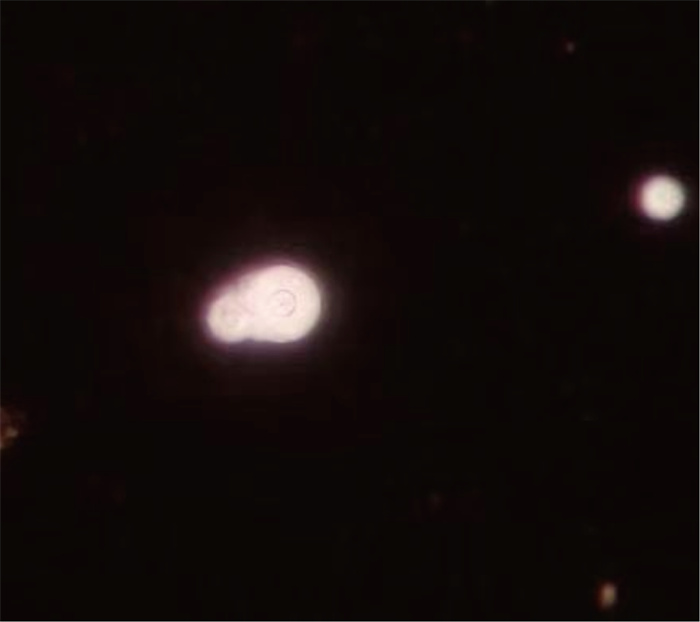

1 病例特点患者为51岁男性,因“头痛10余天”于2023年7月21日就诊于该院。患者既往有“2型糖尿病”病史,家属代诉可疑鸟粪接触史。10余天前患者无明显诱因出现头痛,疼痛部位位于左侧颈枕部及额顶部,呈持续性胀痛,体位变化加重,疼痛未向他处放射,并有一过性失语、间歇性跛行,先就诊于省级医院外科系统完善颈椎计算机断层成像(computed tomography,CT)提示:颈椎退行性变;C4/5椎间盘膨出;项韧带钙化。头颅磁共振成像(magnetic resonance imaging,MRI)和磁共振血管造影(magnetic resonance angiography,MRA)未见异常,患者遂来该院门诊并被收入疼痛科进一步治疗。入院查体生命体征平稳,神志清楚,颈软,定向力正常,双下肢肌力Ⅳ级,浅感觉减弱,完善颈椎MRI提示颈4/5椎间盘突出(右旁中央型),相应脊髓少许变性可能,考虑“颈椎病、脊髓压迫”,遂于2023年7月24日全麻下行“前路颈4/5椎间盘髓核摘除、椎管减压、零切迹椎间融合器植骨融合术”,术后第2天患者头痛无明显好转,并出现谵妄,自行拔除尿管及心电监护,请神经内科会诊考虑颅内感染,并转入神经内科治疗,完善腰椎穿刺检查,脑脊液压力280 mmH2O,脑脊液常规及生化结果提示白细胞295×106/L,以多核细胞为主,总蛋白2 341 mg/L,葡萄糖9.0 mmol/L,氯132.2 mmol/L;完善病原学检测,结果提示脑脊液中隐球菌荚膜抗原阳性(7月25日),墨汁染色涂片找到新型隐球菌(7月25日,见图 1),脑脊液二代测序(metagenomic next generation sequencing,mNGS)检测提示新型隐球菌(7月25日,见图 2),血培养回报培养出新型隐球菌(7月26日,见表 1),同时完善胸部CT提示双肺多发肺结节、空洞(见图 3I~L),不排除隐球菌病变,结合上述病史、体征及辅助检查结果,考虑隐球菌肺炎合并脑膜炎可能性大,经抗感染、脱水降颅压、镇静等对症支持治疗,病情仍在进展,遂于7月25日转入重症监护病房(intensive care unit,ICU)。转入ICU后查体患者意识呈浅昏迷,双侧瞳孔等大等圆,直径约3.5 mm,对光反射迟钝,双侧克氏征阳性,病理征阴性。立即予哌拉西林/他唑巴坦+氯康唑+两性霉素B胆固醇硫酸酯复合物(因氟胞嘧啶需临购暂未用)抗感染、脑保护、脱水降颅压等治疗,转入后第2天患者的意识障碍仍呈进行性加重,深浅反射消失,血氧饱度、心率下降,考虑其颅内压进行性升高,遂行气管插管连接呼吸机辅助通气,加用氟胞嘧啶联合两性霉素B脂质体抗真菌治疗,予腰大池引流缓解脑脊液压力。经上述治疗后患者的意识仍无改善,复查头颅CT后提示弥漫性脑肿胀并脑疝形成(7月27日,见图 3 C和D),出现中枢性尿崩症、凝血功能障碍、先后行双侧去骨瓣减压术+硬脑膜修补术、侧脑室引流,但患者仍处于深昏迷,血压需大剂量血管活性药物维持,2023年8月2日家属要求出院。

| A、B:2023年7月26日头颅CT扫描结果,脑实质未见肿胀,脑沟、脑回结构清晰;C、D:2023年7月27日头颅CT扫描结果,弥漫性脑肿胀,双侧大脑半球灰白质分界不清,脑沟脑裂明显变窄消失,脑室受压变窄;E~H:2023年7月25日头颅MRI扫描结果,左侧额叶皮层见团片状异常信号影,范围约18 mm×40 mm(左右径×前后径),T1WI呈稍低信号,局部见点状稍高信号(E),T2WI呈混杂稍高信号(F),DWI及ADC未见弥散受限(G、H);I~L:2023年7月26日胸部CT扫描结果,双肺下叶见多发斑片状、结节状高密度影,红色箭头所指可见斑片状高密度,黑色箭头所指可见空洞。 A, B: The result of cranial CT scan findings in July 26, 2023. The brain parenchyma was not swollen, and the structures of the sulci and gyrus were clear. C, D: The result of cranial CT scan findings in July 27, 2023. There was diffuse and swelling brain, poorly demarcated gray and white matter in bilateral cerebral hemispheres, marked narrowing and disappearance of the sulcus cerebralis fissure, and narrowing of the ventricles by compression. E-H: The result of cranial MRI scan findings in July 25, 2023. A mass-like abnormal signal shadow was seen in the left frontal cortex, which was about 18 mm×40 mm in extent (right and left diameters × anterior and posterior diameters), with a slightly low signal in T1WI, and localized punctate slightly high signals (E), mixed slightly high signals in T2WI (F), and no diffusion limitation was seen in DWI and ADC (G, H). I-L: The result of chest CT scan in July 26, 2023. Multiple patchy and nodular hyperdense shadows were seen in the lower lobes of both lungs, with patchy hyper density visible as indicated by the red arrows and cavities visible as indicated by the black arrows. 图 3 患者住院治疗期间各部位的影像学表现 Fig. 3 Imaging findings of various sites during hospitalization |

CM患者临床表现无特异性,包括发热、头痛、精神和神经症状,颅内压增高明显(如头痛、恶心呕吐剧烈),病情进展可累及脑神经麻痹(如听力异常、视物模糊)、视盘水肿,脑实质受累可出现感觉、运动异常、癫痫发作、精神异常等。查体可见脑膜刺激征及意识改变等[3]。CM患者脑膜炎性渗出可累及血管壁,继发血管炎,导致血栓及血管闭塞,出现脑梗死[4],该患者头颅MRI亦提示左侧额顶叶皮质缺血(见图 3 E-H)。除此之外,隐球菌性脑膜炎一般伴发肺部感染,但患者仅表现为咳嗽咳痰等非特异性症状,肺隐球菌病CT表现为多发结节/肿块,界限较清楚,主要分布在肺外周或胸膜下区[5]。此病例以头痛为主要症状,前期一直在外科系统以颈椎病诊疗,病情隐匿、进展快且最终脑疝形成,预后不良,而且胸部CT双肺下叶有多发结节、空洞形成(见图 3 I~L),符合肺隐球菌病的影像学特点。